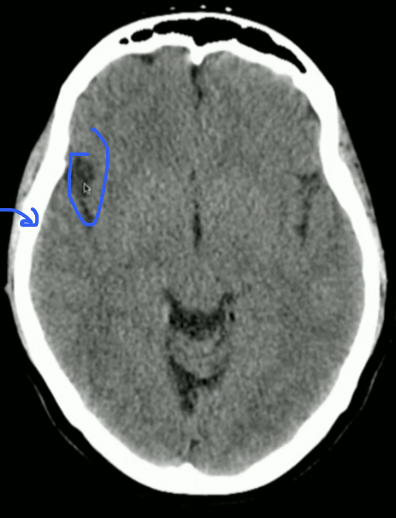

<p>Locate: Sulci, Grey Matter + White Matter</p>

Locate: Sulci, Grey Matter + White Matter

<p>What is this?</p>

What is this?